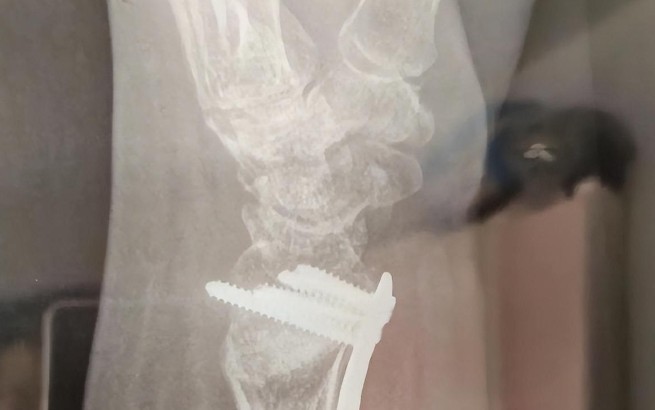

Soñar con una cirugía de muñeca

Soñar con someterse a una cirugía de muñeca indica que necesita realizar cambios fundamentales para resolver un problema grave. La cirugía es un paso necesario para la curación y la recuperación, y puede simbolizar una decisión importante para recuperar sus capacidades o funciones. Soñar con una muñeca rota indica que necesita tomar una decisión importante para superar las dificultades actuales. También puede simbolizar el proceso de aceptar los cambios necesarios en la vida y prepararse para un nuevo comienzo.

Soñar con someterse a una cirugía para tratar una lesión de muñeca

La cirugía para tratar una lesión de muñeca simboliza el proceso necesario para resolver un problema importante en la vida. La cirugía puede ser dolorosa y aterradora, pero es un paso importante para recuperar sus capacidades o funciones. Soñar con una muñeca rota indica que necesita aceptar los cambios necesarios para afrontar los problemas actuales y prepararse para un nuevo comienzo. También puede indicar que necesita tomar una decisión importante para superar los desafíos actuales.